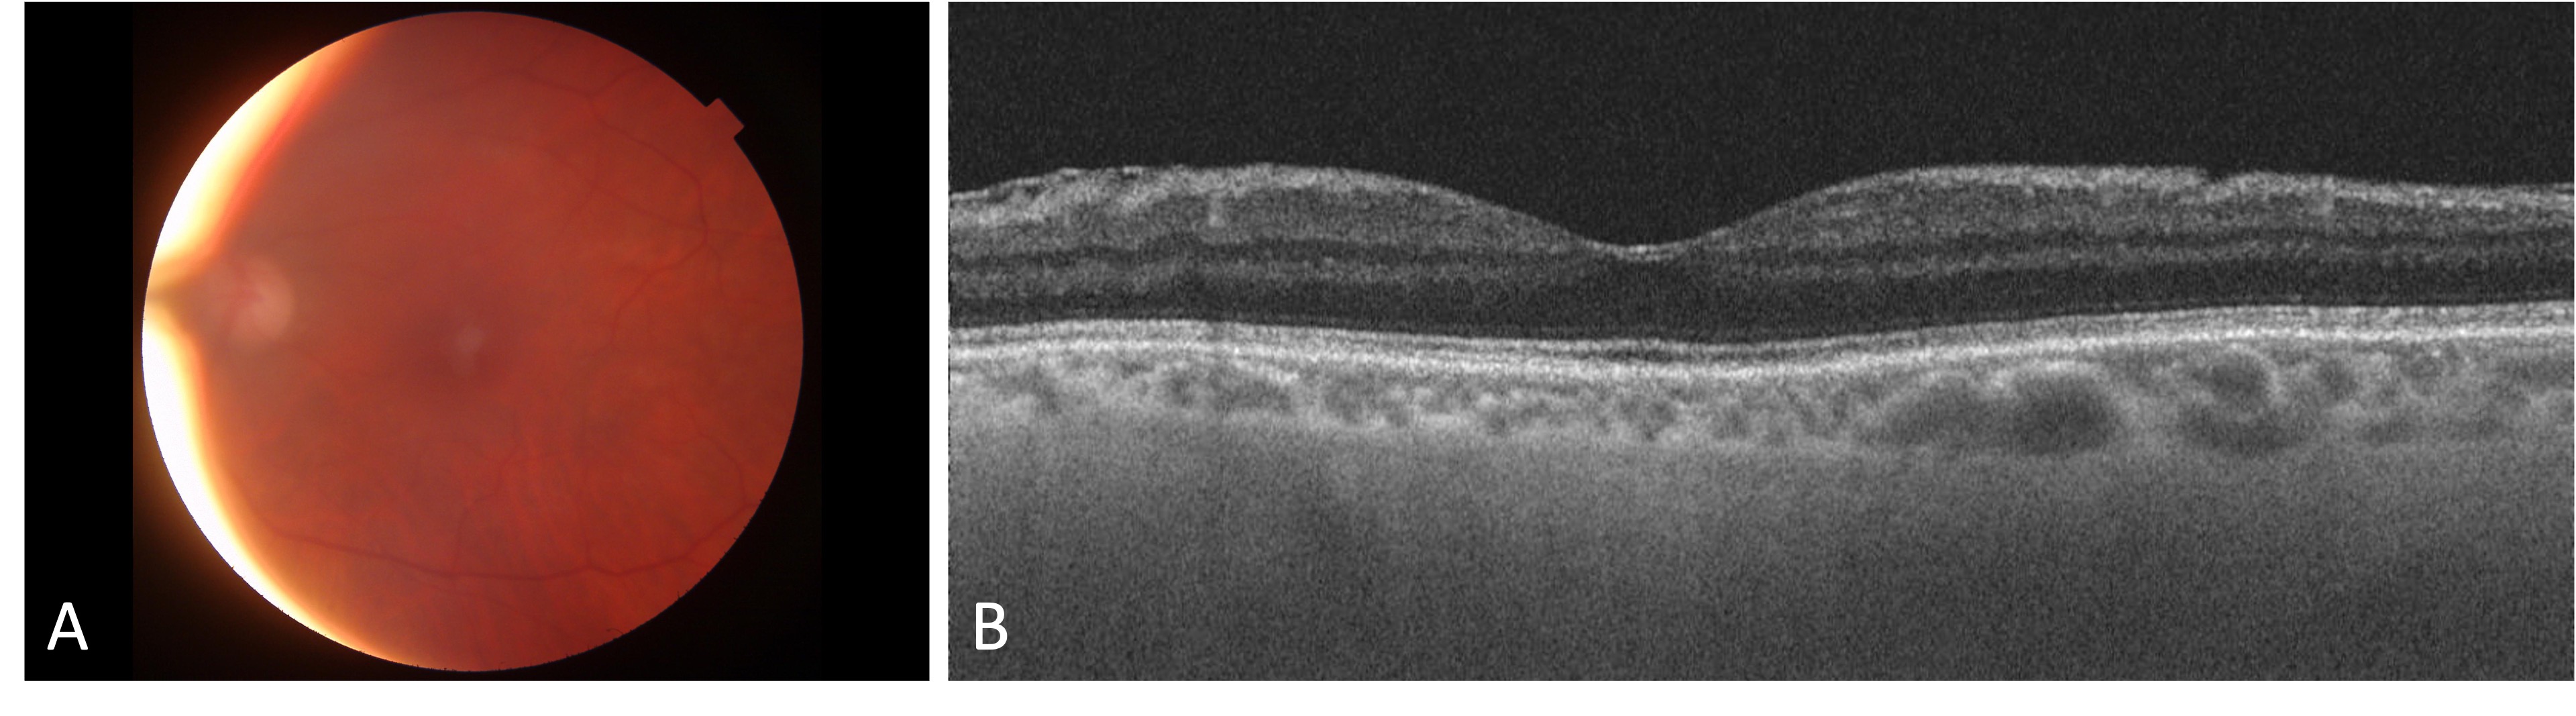

Case presentation: A 67-year-old female with a prior ocular history of bilateral cataract surgery, Fuchs endothelial dystrophy, and pseudophakic DMEK in the left eye presented with endophthalmitis 2 months after keratoplasty. DMEK graft removal without replacement with an intracameral washout, pars plana vitrectomy, intracameral, and intravitreal antibiotics resulted in an excellent visual outcome (20/25).

Conclusion: This is a unique case of late endophthalmitis following DMEK surgery requiring graft removal and pars plana vitrectomy with excellent visual recovery without donor replacement.